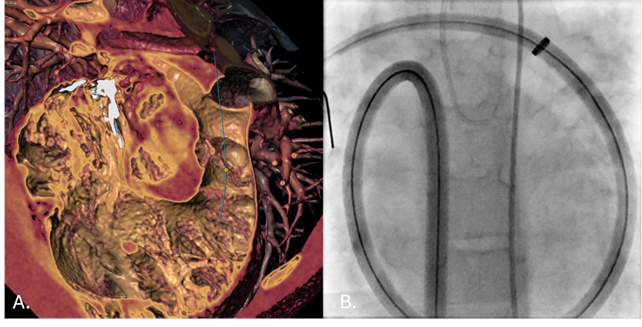

During the first stage, a Lunderquist Extra-Stiff Wire Guide (Cook Medical) was positioned in the distal right pulmonary artery (RPA). Advancement of a 64-cm 16F Sentrant sheath (Medtronic) was hindered by the patient’s size and anatomy. To overcome this, a controlled loop was intentionally created within the right atrium, allowing the sheath to advance smoothly into the RPA without kinking or deformation (Video). An AndraStent XXL 30 (Andramed) was then deployed on a 24 × 40-mm Andra2Balloon (Andramed), successfully establishing a stable landing zone for valve implantation (Figure).